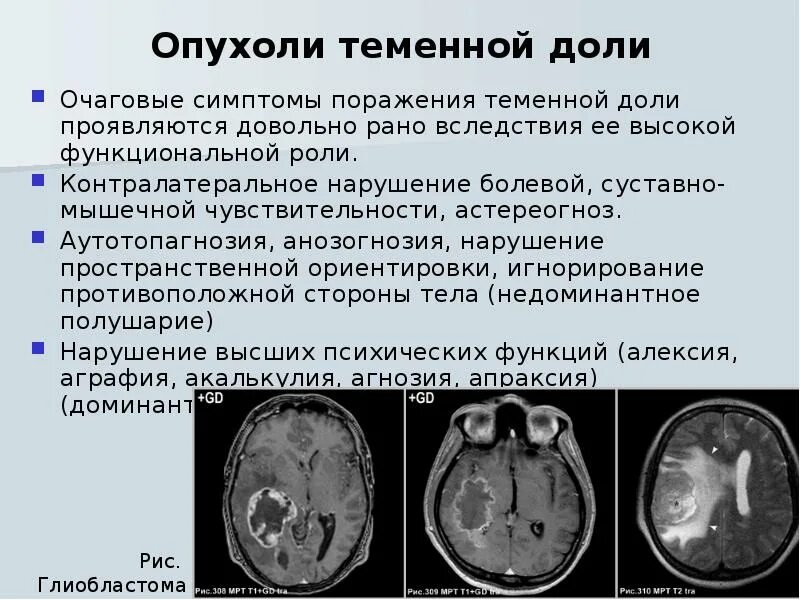

Злокачественные заболевания молочных желез. Новообразование молочной железы. Злокачественная опухоль молочной железы. Доброкачественные новообразования молочной железы. Очаговые симптомы опухоли затылочной доли. Клинические проявления опухоли лобной доли:. Опухоль мозга височной доли симптомы. Опухоль затылочной доли головного мозга.

Очаговые симптомы опухоли затылочной доли. Клинические проявления опухоли лобной доли:. Опухоль мозга височной доли симптомы. Опухоль затылочной доли головного мозга. Гепатомегалия. Симптомы гепатомегалии. Умеренное увеличение печени. Умеренная гепатомегалия.

Фиброаденома молочной железы дифференциальный диагноз. Новообразование молочной железы фиброаденома. Диф диагноз фиброаденомы молочной железы. Фиброаденома молочной железы 30мм-37мм. Диагностические критерии глиомы головного мозга. Особенности опухолей лобной доли. Клиника опухоли затылочной доли головного мозга. Симптомы, характерные для опухолей лобной доли.

Диагностические критерии глиомы головного мозга. Особенности опухолей лобной доли. Клиника опухоли затылочной доли головного мозга. Симптомы, характерные для опухолей лобной доли. Компьютерная томография с болюсным контрастированием. Кт толстой кишки с контрастированием. Кт с болюсным контрастированием что это.

Злокачественные новообразования печени кт. Объемное образование печени на кт. Клиника опухолей височной доли. Опухоль височной доли головного мозга диагностика. Симптомы поражения лобной доли головного мозга опухоль. Очаговые симптомы опухоли височной доли.

Клиника опухолей височной доли. Опухоль височной доли головного мозга диагностика. Симптомы поражения лобной доли головного мозга опухоль. Очаговые симптомы опухоли височной доли. Проявления поражения теменной доли.. Объемное образование головного мозга.